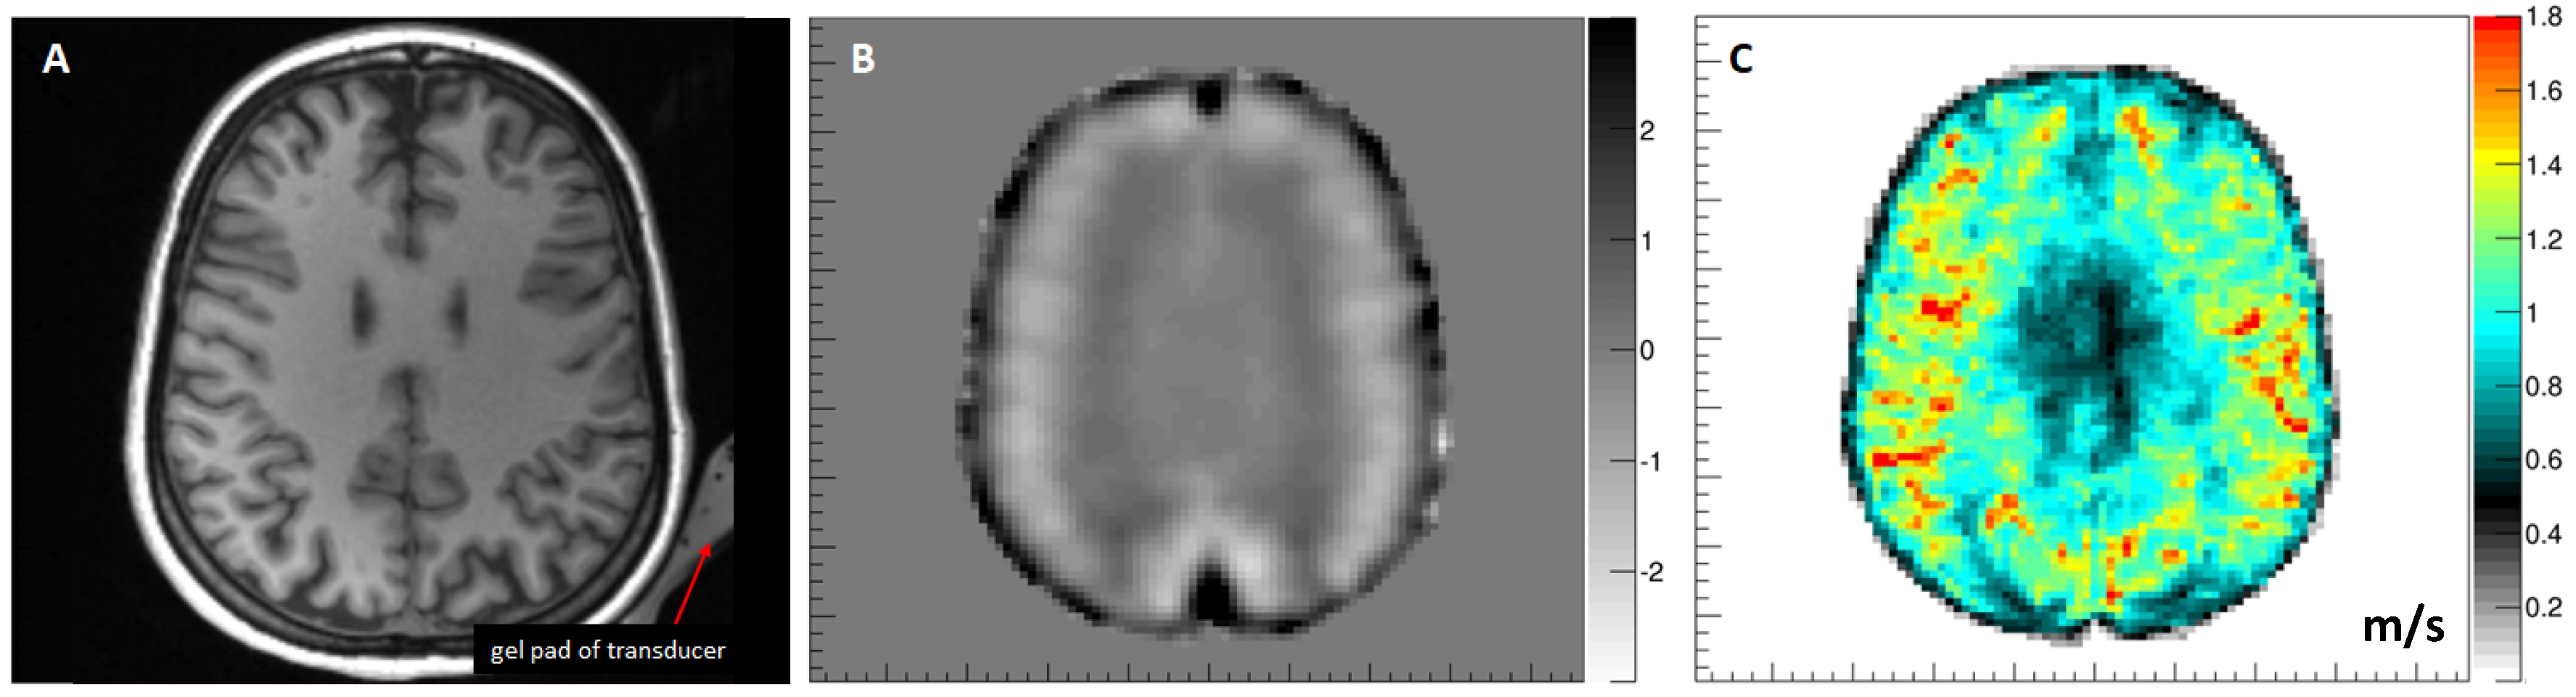

5.5. Brain